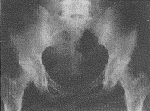

患者男,30岁,体检时发现。查体:无阳性体征。实验室检查:血钙、血磷均正常。X线及CT所见(图1、2):双侧髂骨、髋臼、股骨头及颈部骨松质内见大小不一、圆形及类圆形致密影、边界清晰、直径约0.3~2cm不等。诊断:骨斑点症。

图2